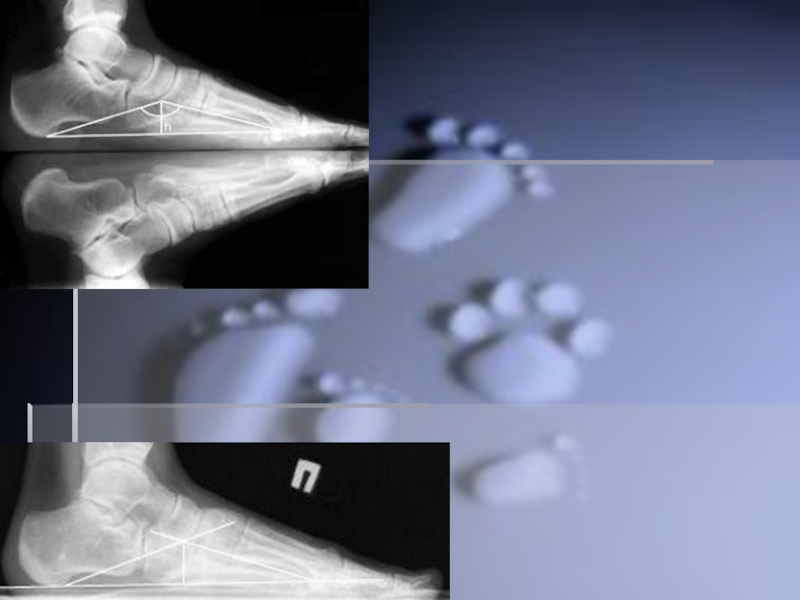

Слайд 35∙ Рентгенодиагностика

∙ Рентгенодиагностика

Слайд 36Методы исследования

Методы исследования

Слайд 42Другим методом диагностики продольного плоскостопия является измерение расстояния между бугристостью ладьевидной

кости (костный выступ, находящийся ниже и кпереди от медиальной лодыжки) и поверхностью опоры. Измерение проводят обычной сантиметровой линейкой в положении осматриваемого лица стоя (рис. 5). У взрослых мужчин это расстояние должно быть не менее 4 см, у взрослых женщин – не менее 3 см. Если соответствующие цифры ниже указанных границ, констатируется понижение продольного свода